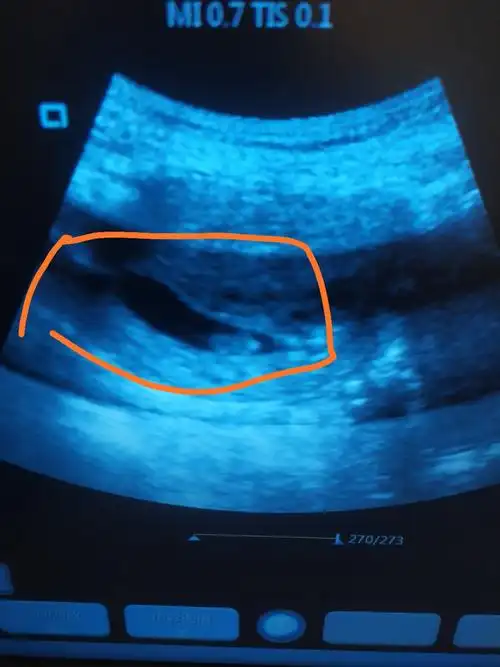

诊断 处理发病以来,未用药,二便正常,无腹痛随访 讨论停经43天,阴道不